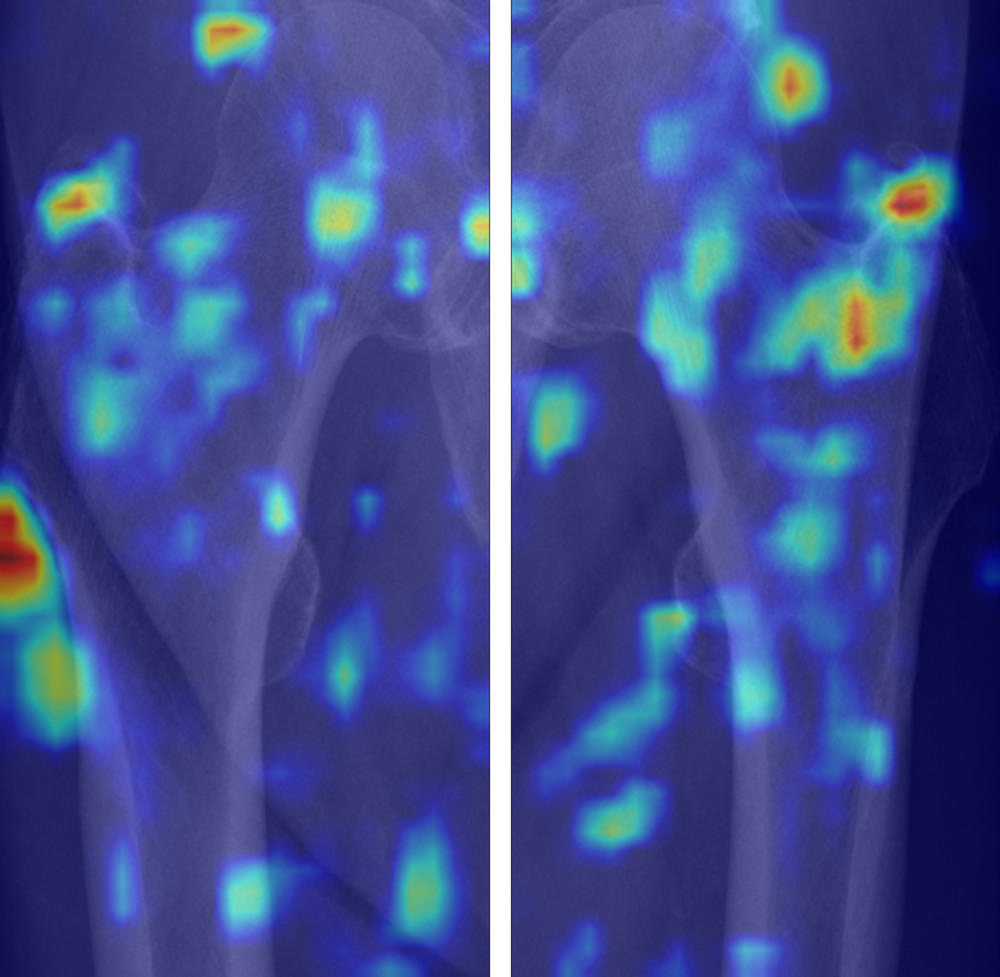

Figure 6. Gradient-weighted class activation mapping (Grad-CAM) images of true-positive cases for diagnosis of osteoporosis. True-positive cases highlighted the medial cortex and lateral surrounding soft tissue area, which reflect the cortical thinning and incremental role of surrounding soft tissue for predicting osteoporosis. We used the jet colormap scale, where the red color stands for high relevance, yellow for medium relevance, and blue for low relevance.

High-res (TIF) version